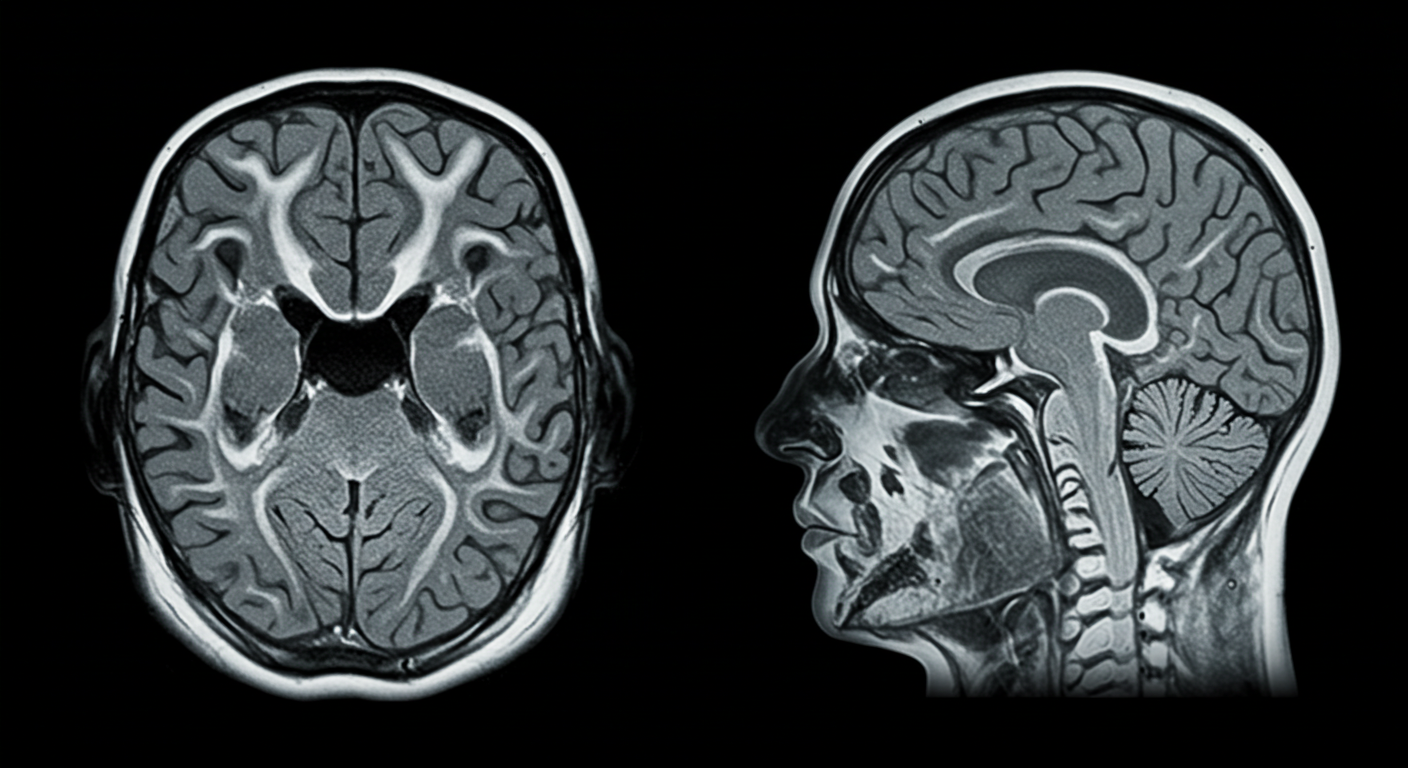

**뇌MRI(Magnetic Resonance Imaging)**는 강력한 자기장을 이용해 뇌의 구조와 이상을 상세히 촬영하는 비침습적 검사입니다. CT나 X-ray와 달리 방사선 노출이 없고, 뇌혈관, 뇌조직, 종양, 염증, 퇴행성 변화까지 정밀하게 확인할 수 있습니다.

- 고해상도 이미지로 미세한 병변까지 감지

💡 특히 고령자에게 흔한 치매, 뇌졸중, 뇌종양 등을 조기에 발견하는 데 매우 효과적입니다.